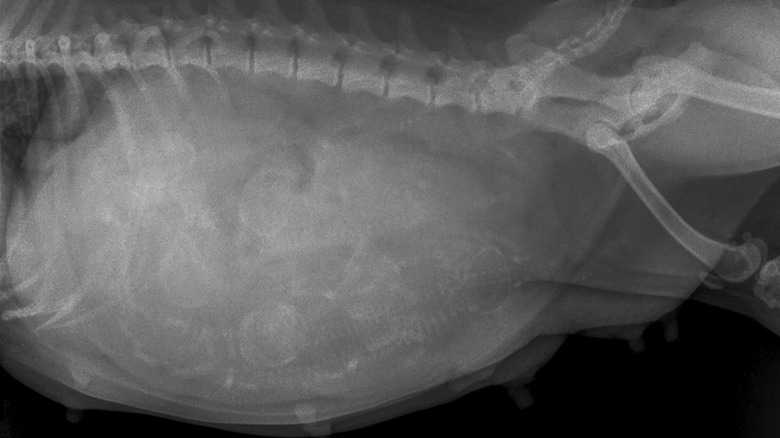

As your dog gets closer to her due date, your veterinarian can confirm the size and number of puppies through an X-ray. The X-ray will pick up the puppy's skulls and vertebrae and can help you estimate the number of puppies to expect. This is beneficial for when your dog goes into labor, as you'll be able to determine when she's had all of her puppies.